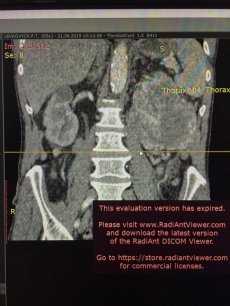

«Прооперовані 2 пацієнта з різних куточків України, з великими, надзвичайно складними пухлинами нирки та пухлиною позаочеревинного простору», - йдеться у повідомленні.

У першому випадку операція тривала годину і двадцять хвилин. Пацієнту проводили радикальну нефректомію (операція з видалення нирки, - прим.авт.) Під час операції медики також видалили пухлину вагою 2 кілограми.

Другому пацієнту видаляли пухлину позаочеревинного простору. Операція тривала годину і 40 хвилин. Маса пухлини – 1,5 кілограма.